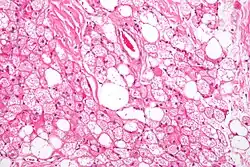

In contrast to white adipocytes, which contain a single lipid droplet, brown adipocytes contain numerous smaller droplets and a much higher number of (iron-containing) mitochondria, which gives the tissue its color.[3] Brown fat also contains more capillaries than white fat. These supply the tissue with oxygen and nutrients and distribute the produced heat throughout the body.

Brown fat in humans in the scientific and popular literature refers to two cell populations defined by both anatomical location and cellular morphology. Both share the presence of small lipid droplets and numerous iron-rich mitochondria, giving the brown appearance.

- "Classical" brown fat is found in highly vascularized deposits in somewhat consistent anatomical locations, such as between the shoulder blades, surrounding the kidneys, the neck, and supraclavicular area, and along the spinal cord. This is the smaller of the two types and has numerous small lipid droplets.

- Beige fat is the adrenergically inducible cell type that is dispersed throughout adipose tissue. It has greater variability in lipid droplet size and a greater proportion of mitochondria to lipid droplets than white fat, giving it a light brown appearance.[18] In mouse and human organoid models, EPAC1 (exchange proteins directly activated by cAMP) was reported to preferentially increase the production of beige fat relative to WAT.[19]